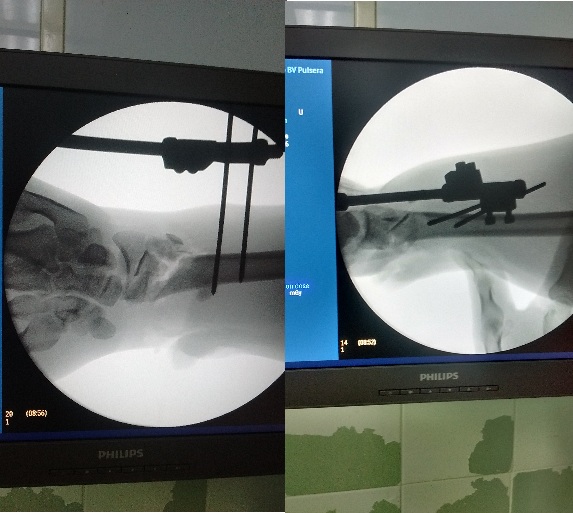

Al tener en cuenta todos los elementos anteriores, se decide llevar el paciente al quirófano, para tratamiento de tipo quirúrgico, se realizó limpieza y desbridamiento de la herida en la muñeca que comunicaba con el foco de fractura distal del radio, se concluyó la extracción del cúbito en su totalidad carente de partes blandas adheridas. Se colocó fijación externa monopolar tipo RALCA ® con el objetivo de estabilizar la muñeca (figura 4).

Luego se aplicó inmovilización para estabilizar la fractura del radio proximal, la que en 15 días posteriores fue fijada con placa y tornillos de la Asociación para la Osteosíntesis (AO) de 4,5 milímetros. En relación al tobillo izquierdo, en el mismo acto quirúrgico de urgencia se realizó la reducción cerrada y su comprobación mediante radiografía simple anteroposterior y lateral.